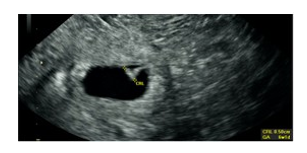

The patient’s post-operative course was unremarkable. She received 1 unit of PRBCs post operatively. An official obstetrical ultrasound was performed on post-operative day (POD) #0 re-confirming the presence of a viable IUP, dated 6.1 weeks with a 2.4 cm sub chorionic bleed (Fig 5-6). The patient was discharged on POD#1. She went on to have a full term spontaneous vaginal delivery of the remaining IUP. Of note, upon chart review, it was noted that the patient was diagnosed with 2 separate episodes of gonorrhea and chlamydia, 6 and 11 years prior, respectively. Both infections had been treated and followed by a negative test of cure. The patient, upon the initial encounter in the ED, did not report this information. Due to the urgent nature of her presentation, she was not immediately assigned to her electronic medical chart, but instead received a temporary chart to allow for her immediate management.

Figure 5: ultrasound imaging of the single IUP; Crown Rump Length is 0.5cm consistent with 6.1week gestational age with fetal cardiac activity of 113BPM